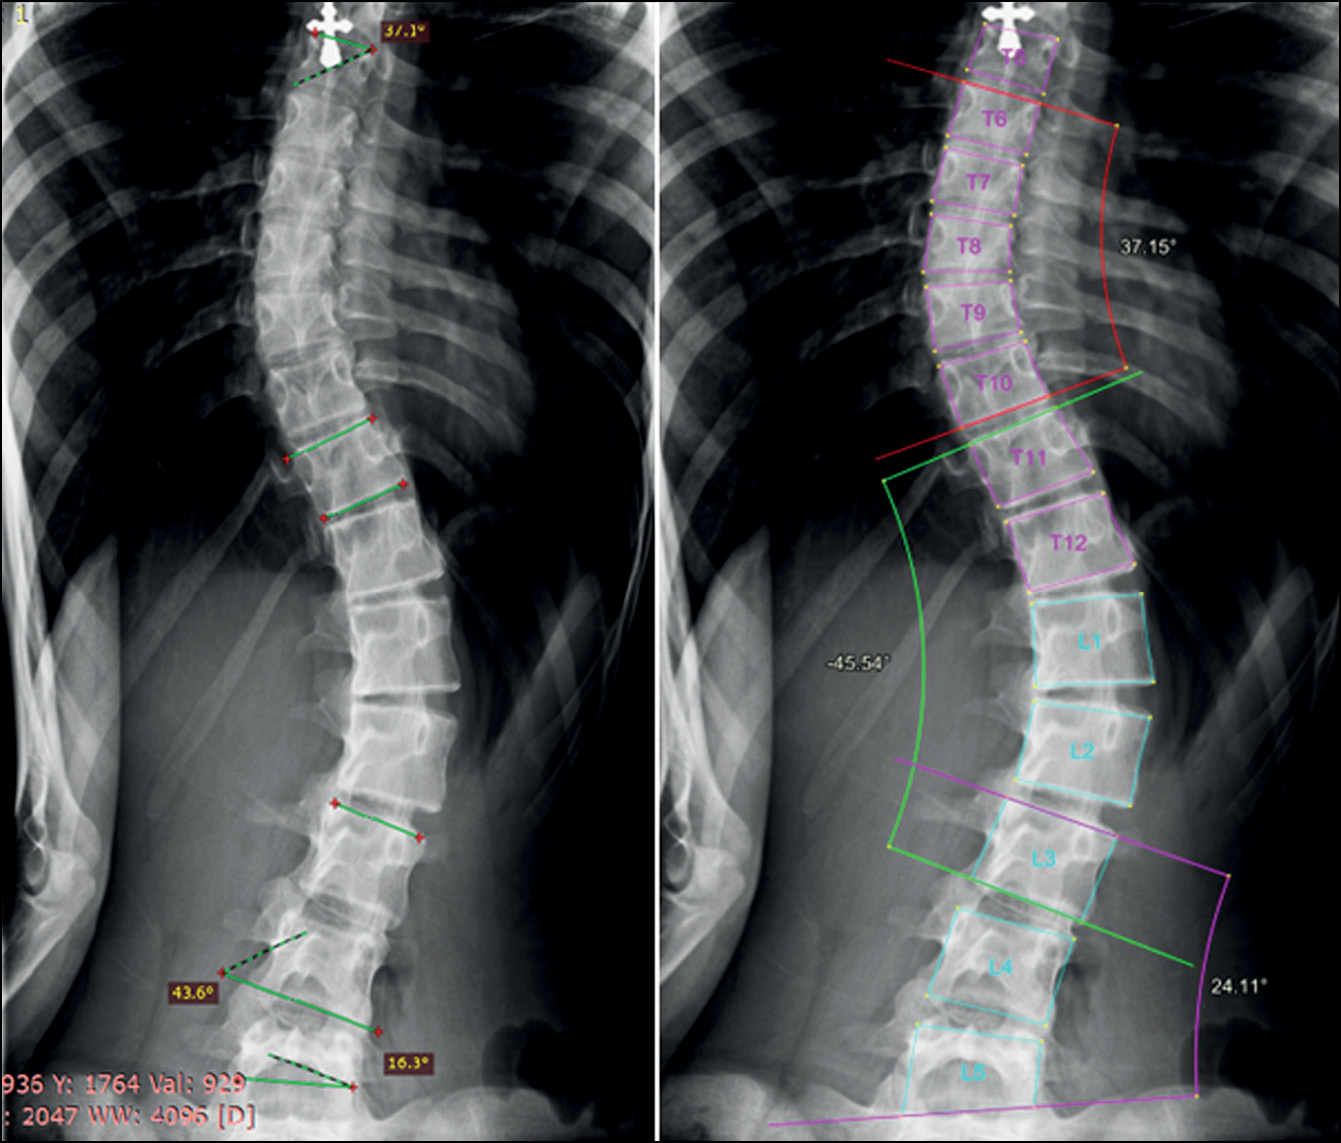

The bulk of this work was performed in a hospital where adolescents are screened for scoliosis, as part of multiple examinations for medical commissions, to determine whether adolescents match the criteria for army enlistment. Thus, radiographs in test set 1 and test set 2 were divided according to the severity classification included in Federal Law No. 565, where any small curves with angles <10° are considered grade 1 scoliosis [16]. The new automatic system for evaluating scoliosis on digital radiographs can help radiologists to define the scoliosis grade and measure the curve’s angle, particularly in situations such as screening for scoliosis and at times of heavy workload in outpatient clinics. In these situations, radiologists can use the program as an objective tool, increasing the accuracy of scoliosis evaluation on frontal radiographs because the interobserver variability can be avoided if radiologists use the same instrument. Moreover, it can significantly save the radiologist’s time. In addition, Cobb’s angles measured by the system were acceptable, with no significant clinical variability in most of the evaluated curves. Fig. 4 shows an example of how the system works.

Fig. 4. X-ray image showing grade 2 scoliosis. Analysis by the system (left) and by the radiologist (right). The radiologist did not measure the thoracolumbar curve as the lower EV is not shown in the image.

In addition, in most cases, the system accurately evaluated radiographs with severe scoliosis (grades III and IV), although errors in vertebral detection and numbering or errors in measuring Cobb’s angle sometimes were noted. Grade IV scoliosis is characterized by maximum vertebral rotation, with displacement of the pedicle beyond the midline and deformation of the vertebral body. Thus, the usual shape of the vertebra changes, and the edges of its body become less defined (Fig. 9).

Fig. 9. Specifications of vertebral marking in radiographs with grade 3 and 4 scoliosis. Errors in detection and numbering of vertebrae caused by the unusual shape of the vertebrae (yellow arrow).